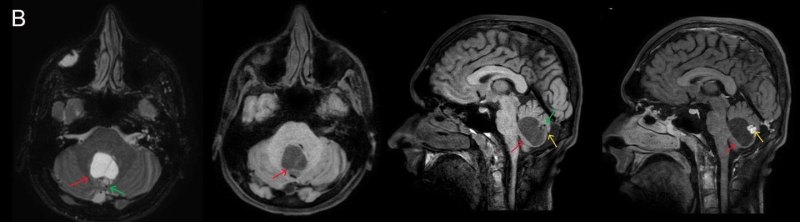

- A) Beyin BT incelemede; posterior fossada hipodens, düzgün sınırlı kistle beraber (oklar), posteriorunda 8 mm boyutunda, iyi sınırlı, kontrastsız BT’de parankim ile izodens, postkontrast görüntülerde yoğun kontrast tutulumu gösteren mural nodül komponenti (oklar) gözlenmektedir.

- B) Beyin MRG incelemesinde; 4. ventriküle bası etkisi oluşturan yaklaşık 3.5 cm boyutta, T2A hiperintens T1A hipointens kistik komponent (oklar) ve posteriorunda T1 ve T2A serilerde parankim ile izointens, içerisinde flow void alanların (oklar) izlendiği, post kontrast görüntülerde yoğun kontrast tutulumu gösteren mural nodül (oklar) barındıran düzgün sınırlı lezyon izlenmektedir.

- Kistik komponent: T1A hipointens, T2A hiperintens

- Mural nodül: T1A izo-hipointens, T2A orta derecede hiperintens olabilir.

- Kontrastlı incelemelerde mural nodül belirgin ve yoğun kontrast tutulumu gösterir. Ancak kist duvarında genellikle kontrastlanma beklenmez.

- T1 ve T2A görüntülerde flow voidler sıktır.